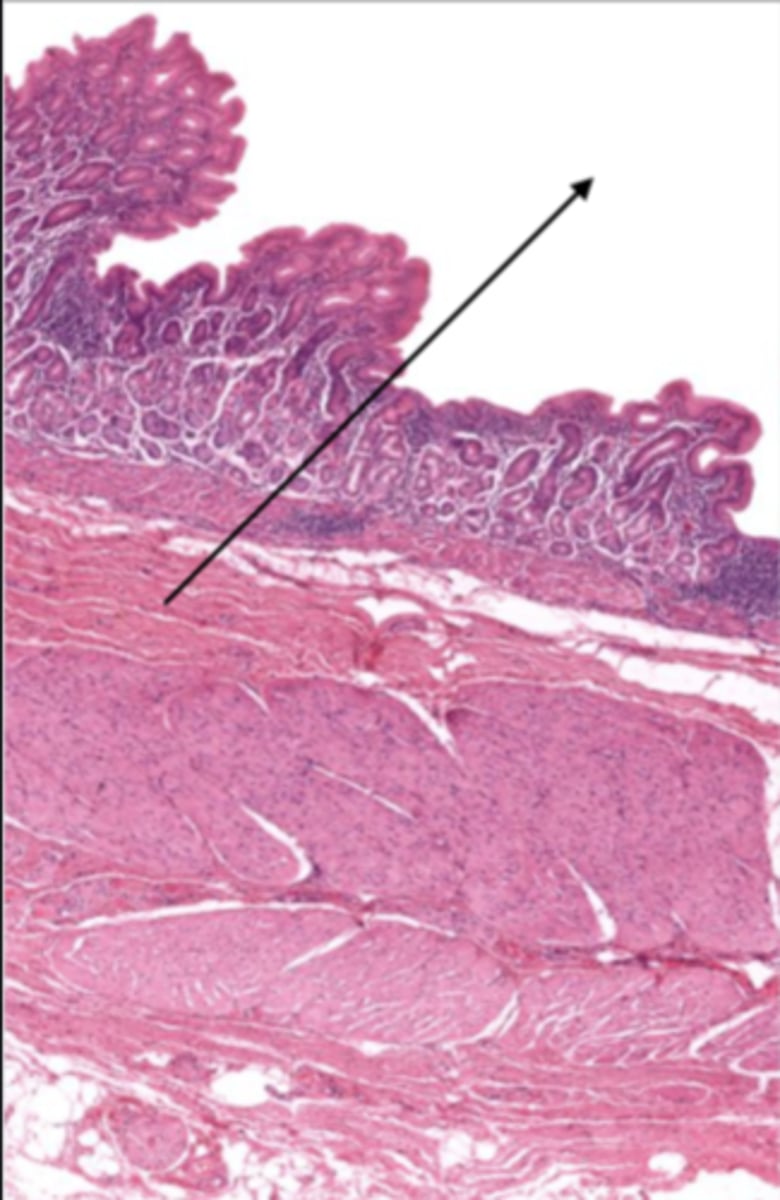

gallbladder (histology)

gallbladder

this tissue's wall structures/layers are different than the rest of the organs

simple columnar epithelium

lumen (gallbladder)

mucosa (gallbladder)

mucosal epithelium (gallbladder)

lamina propria (gallbladder)

muscularis mucosa and submucosa

gallbladder tissue does not have _______ and ______

muscularis externa (gallbladder)

serosa/adventitia (gallbladder)